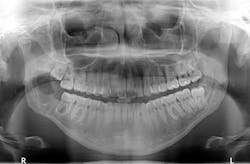

Clinical examination revealed inflamed tissue circa partially erupted No. 32 extending up to the distal of no. 2. The area intraorally was tender to palpation, but unremarkable extraorally. A panoramic X-ray was taken and a large radiolucent lesion was noted to extend from the distal of no. 1 to the distal of no. 32. A significant portion of bone destruction in the mandible was also observed. In addition, a radiolucency was seen distal to the crown on no. 17.

Our main concern was the extent of destruction—fracture potential and permanent paresthesia was extremely high. Following surgery, the patient was placed on a liquid diet for six to eight weeks. The specimen was sent to pathology. Diagnosis: dentigerous cyst. Follow-up over the course of the last year has proved to be promising—the bone has filled in, the patient has regained some feeling on the lower right side of her jaw and, thus far, there have been no recurrent or metastatic lesions observed. We are monitoring no. 17 and plan to remove it and the associated radiolucency when the bone has healed sufficiently in the right mandible.